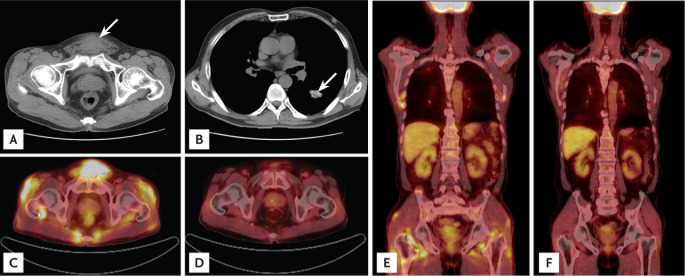

A 61-year-old Korean man presented to the hospital with a progressively enlarging suprapubic mass. He had been diagnosed with diabetes mellitus and hypertension 10 years previously. Two years before admission, he was diagnosed with membranous nephropathy and treated with cyclosporine and prednisolone. At that time, his creatinine (Cr) level was 1.53 mg/dL. A physical examination revealed a firm, nontender, round, fixed mass without skin lesions in the suprapubic area. There was no palpable lymphadenopathy or hepatosplenomegaly. Initial laboratory findings showed serum Cr and serum calcium (Ca) levels of 2.0 and 11.0 mg/dL, respectively. After 12 days, the serum Cr and Ca levels increased to 6.2 and 14.7 mg/dL, respectively. Other laboratory results were as follows: serum level of blood urea nitrogen, 55.9 mg/dL; ionized Ca, 1.91 mmol/L (reference range, 1.13 to 1.32); phosphorous, 4.5 mg/dL; intact parathyroid hormone, 8.1 pg/mL (reference range, 14 to 72); serum alkaline phosphatase, 47 IU/L (reference range, 42 to 128); 1,25-dihydroxyvitamin D, 71.2 pg/mL (reference range, 25.1 to 66.1); parathyroid hormone related peptide, < 1.1 pmol/L; angiotensin-converting enzyme, 110.2 U/mL (reference range, 9 to 47); thyroid-stimulating hormone, 0.706 µIU/mL; hemoglobin, 12.1 g/dL; white blood cell count, 9.8 × 103/µL; platelet count, 370 × 103/µL; urine Ca/Cr ratio, 303 mg/g; and 24-hour urine protein, 312.8 mg/day. Abdominal computed tomography (CT) revealed a 4.4 × 3.3-cm suprapubic mass in the subcutaneous area (Fig. 1A). A chest CT scan showed did not show hilar lymphadenopathy (Fig. 1B). 18F-fluorodeoxyglucose positron emission tomography/CT (18F-FDG PET/CT) showed multiple foci of hypermetabolic activity in the suprapubic area, both shoulders, flank, hip, and thigh, and there were no hypermetabolic lesions in the lung (Fig. 1C and 1E). He was treated with intravenous fluids, furosemide, bisphosphonate, calcitonin, and renal replacement therapy (continuous venovenous hemodialysis). However, his Ca and Cr levels were persistently elevated at 11.0 and 5.1 mg/dL, respectively. The suprapubic mass was excised and histologically identified as noncaseating granulomatous inflammation within fat tissue. The solid granuloma was composed of epithelioid histiocytes and multinucleated giant cells engulfing fat vacuoles and mild lymphocytic infiltration (Fig. 2). The patient was started on oral prednisolone 30 mg/day, and his Ca level decreased to 9.6 mg/dL after 1 week of treatment. After 2 weeks, his Cr level improved to 2.3 mg/dL (Fig. 3). Prednisolone was slowly tapered off over 3 months. After 3 months of treatment, a follow-up 18F-FDG PET/CT scan demonstrated complete resolution of the multiple hypermetabolic lesions (Fig. 1D and 1F), and his Cr and Ca levels were 2.0 and 8.8 mg/dL, respectively. His renal function and serum Ca levels remain stable after 1 year of treatment. The subcutaneous sarcoidosis associated with hypercalcemia and AKI was successfully treated with a moderate dose of prednisolone.

In this case, the patient presented with a single large mass in the suprapubic area. There was no bilateral hilar lymphadenopathy or palpable lesion other than the suprapubic mass. Additionally, the patient showed severe hypercalcemia and AKI, which is a rare presentation of subcutaneous sarcoidosis [4]. Malignancies such as lymphoma and soft tissue sarcoma were considered as differential diagnoses. The diagnosis of subcutaneous sarcoidosis was based on the patient's clinical and radiological findings and supported by the histopathological findings of a noncaseating epithelioid granuloma predominantly involving panniculus with minimal inflammation and without evidence of organisms or exogenous particles [1,3]. The sarcoidosis was characterized by infiltration of CD4 type 1 helper cells and macrophages into the sites of inflammation, and these cells increased the 18F-FDG uptake [5]. 18F-FDG PET/CT scans showed good sensitivity (87%) in detecting all biopsy-proven sarcoidosis localizations excluding skin involvement [5]. 18F-FDG PET/CT revealed multiple sites of involvement in the subcutaneous and muscle layers at the time of diagnosis, and complete resolution of the lesions was seen after the prednisolone treatment. 18F-FDG PET/CT was useful in evaluating the extent of disease and follow-up response to therapy in this patient.

Figure 1

Imaging findings in a patient with subcutaneous sarcoidosis. (A) Abdominal computed tomography (CT) scan showing a 4.4 × 3.3-cm suprapubic mass in the subcutaneous area (arrow). (B) Chest CT scan showing lobulated, calcified nodules in the left lower lung (arrow) and fibrotic scars in the right upper lung, suggesting sequelae of tuberculosis. There were no other lymphadenopathies. (C, E) 18F-fluorodeoxyglucose positron emission tomography (18F-FDG PET)/CT scan showing multiple foci of hypermetabolic activity in the suprapubic area, both shoulders, flank, hip, and thigh; no hypermetabolic lesions are seen in the lung. (D, F) Follow-up 18F-FDG PET/CT scan showing complete resolution of the multiple hypermetabolic lesions after 3 months of treatment.